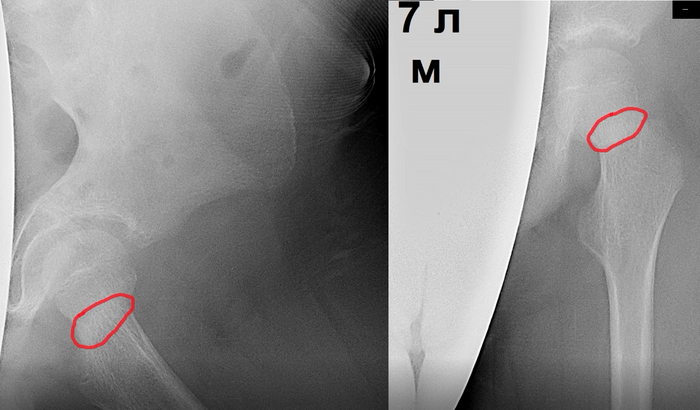

Однажды к нам в травмпункт обратились с семилетним ребёнком аутистом. Из-за своего заболевания он был абсолютно неконтактным, то есть не разговаривал и не мог ничего объяснить. Со слов родителей, травма произошла семь дней назад, ребёнок упал с кровати на левый бок, после чего самостоятельно встал и все эти дни нормально ходил, но не переставал хромать.

К нам в кабинет ребёнок зашёл сам. При ходьбе он щадил левую ногу, стараясь не сгибать её в тазобедренном суставе. Во время визуального осмотра всё было нормально, ни отёка, ни ссадин, ни синяков, никаких повреждений. Когда я начал проверять движения в левом тазобедренном суставе, то он напрягся, но не закричал. Все движения были в полном объёме. Осевая нагрузка на бедренную кость была безболезненна, он как-будто вообще не замечал, что я давлю на неё. На рентгене шейка бедра показалась нам очень подозрительной.

И хотя ребёнок ходил, данное затемнение мы расценили как перелом шейки бедра и направили его в стационар.

Ещё через две недели родители снова привели ко мне этого ребёнка и рассказали, что из больницы их, оказывается, отправили домой. Врачи сочли рентгенологическую картину сомнительной. Не поверили, что человек может ходить при сломанной шейке бедра и сняли диагноз "перелом". Тем не менее, хромота не проходила и даже усилилась, в связи с чем пациента привели ко мне снова. Осмотрев ребёнка ещё раз, я заметил укорочение левой ноги по сравнению с правой. И объём движений в тазобедренном суставе на этот раз был ограниченным. Мы тут же сделали еще один снимок, на котором увидели уже срастающийся перелом шейки бедра со смещением.

Ребёнка сразу повторно направили в больницу, но время уже было упущено. Оперировать было поздно. Далее пострадавшего закатали в гипс и в течение месяца продержали на постельном режиме. Шейка бедренной кости сраслась, но неровно, из-за чего у пациента осталось укорочение левой нижней конечности и хромота. К психиатрическим проблемам добавились ортопедические, у родителей появилась ещё одна головная боль.

Последние снимки: